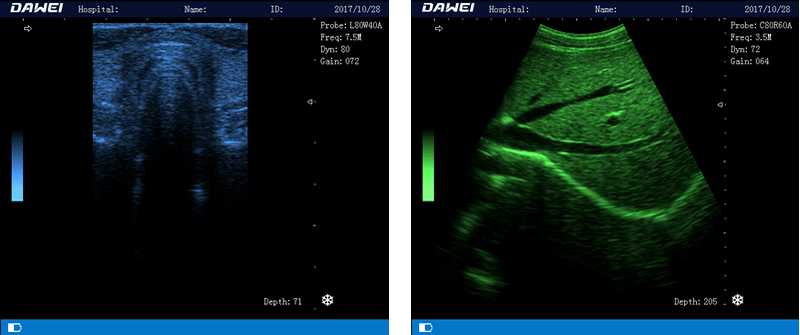

DW-580

筆記本全數(shù)字超聲診斷儀

1.優(yōu)質(zhì)的數(shù)字成像技術(shù),圖像更清晰

5.體積小巧,圖像清晰,操作方便,續(xù)航能力強